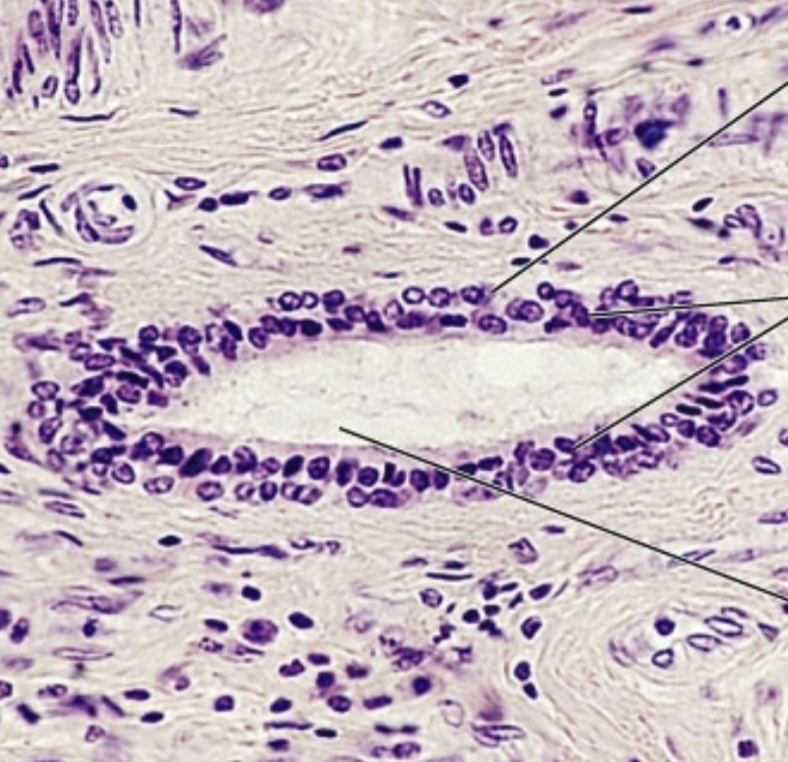

Pseudostratified ciliated columnar epithelium

of Pseudostratified ciliated columnar epithelium

Location: respiratory tract

Function: secretes substances, specifically mucus